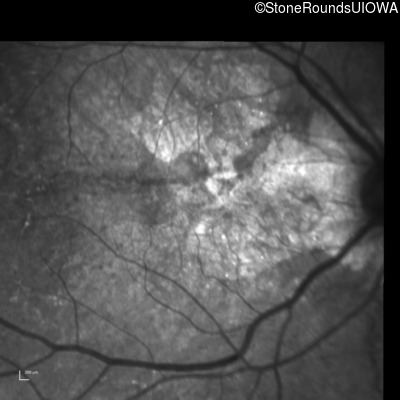

Infrared Fundus Photograph - Right - 20/25 +1

Exemplar